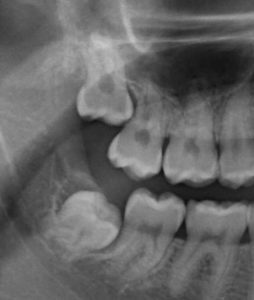

This area is always chronically Q. Simple Extraction 75-200 per tooth 300-1000 all four. How much does it cost to remove wisdom teeth nz - Impacted wisdom teeth very often have a flap of gum over the back.

A simple wisdom tooth extraction where the tooth is fully erupted from the gums and has simple roots using a local anesthetic costs about 75-200 per tooth or 300-800 to have all four wisdom teeth removed as simple non-surgical extractions. For wisdom teeth that are likely to cause problems we recommend that the ideal time for removing wisdom teeth is between the ages of 17-25 years. Getting teeth removed under sedation is more expensive.

For an impacted tooth extraction using a local anesthetic can cost 225-600 per tooth. People who get their impacted wisdom teeth removed when they are young in general have lesser risk of complications and the healing period is much quicker. At Wellington dentists the cost will be 220-480 for one wisdom tooth depending on complexity for two wisdom teeth it would be between 350-960 for three between 520-1300 and four between 800-1700.